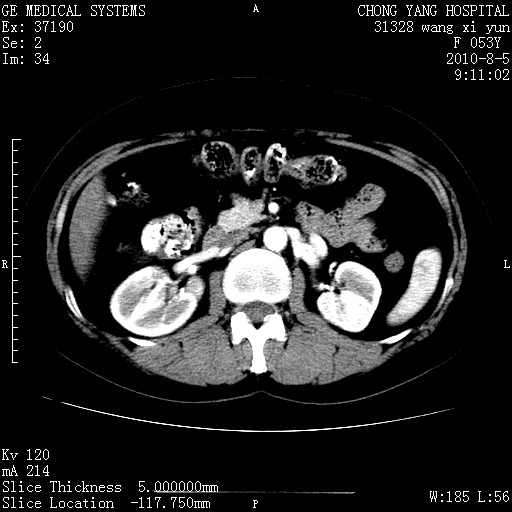

标题: CT28214:F41Y 血尿二十天,建议盆腔平扫加增强。

1)考虑肝左叶胆管细胞癌。2)脂肪肝。

支持胆管细胞ca。